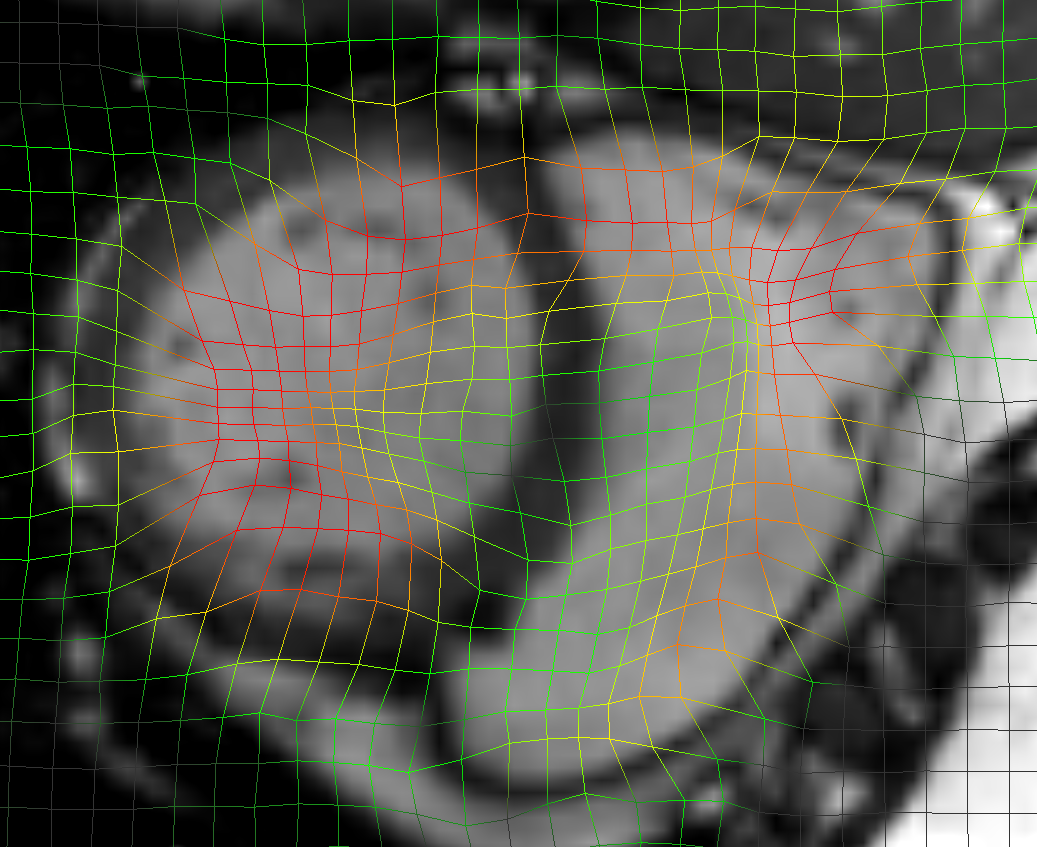

Refer to caption a) DirLab08 deformation grid for inhale to exhale registration Refer to caption b) DirLab08 with overlayed image foldings (Jacobi determinant << 0) Refer to caption c) DirLab08 registration error

Figure 5: This figures show an analysis for two test cases that resulted in the worst results for 3D registration evaluation. The first row shows the extreme inhale phase of dataset Dirlab08 with overlayed deformation grid (a), Jacobi determinant (b) and registration error (c). The patient had a very strong sheering motion along the ribcage in caudal direction which could not be fully captured by our network. The second row shows the extreme diastolic phase for the dataset SC-N-3 with overlayed deformation grid (d) and Jacobi determinant (e) and the extreme systolic phase with contours of the left ventricle (f).